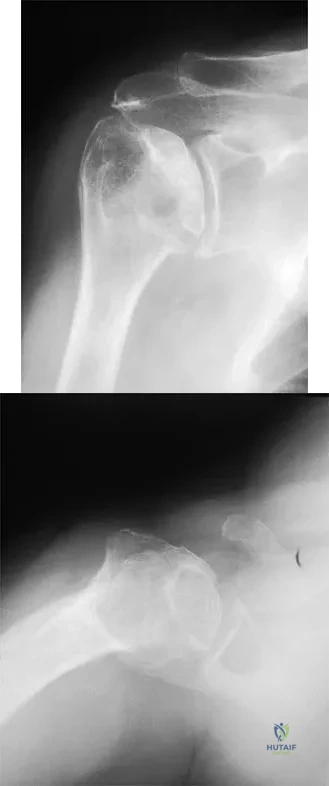

A 45-year-old woman has had progressive right shoulder pain for the past 6 months. She notes that the pain disrupts her sleep, she has pain at rest that requires the use of narcotic analgesics, and she has limited use of her left shoulder for most activities of daily living. History reveals the use of corticosteroids for systemic lupus erythematosus. Examination shows diminished range of motion. Radiographs of the right shoulder are shown in Figures 4a and 4b. Treatment should consist of

Explanation